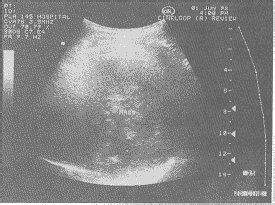

B超检查:

B型超声波检查最早在妊娠第5周(35天),就是月经推迟一周(7天),在B型超声波屏上就可显示出子宫内有圆形的光环,又称妊娠环,环内的暗区为羊水,其中还可见有节律的胎心搏动。所以用B超诊断早孕是最正确可靠的方法。